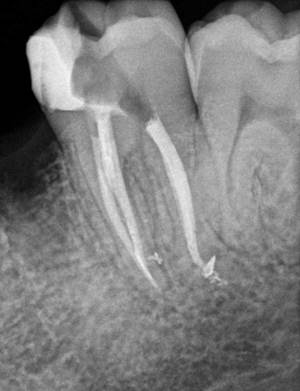

1. Diente con conductos calcificados

Imagen clínica y radiografía mostrando la localización de conductos calcificados.

Radiografía de endodoncia finalizada de molar mandibular con mucha curvatura en la raíz mesial y donde se observan conductos laterales en ambas raíces que hemos conseguido sellar.